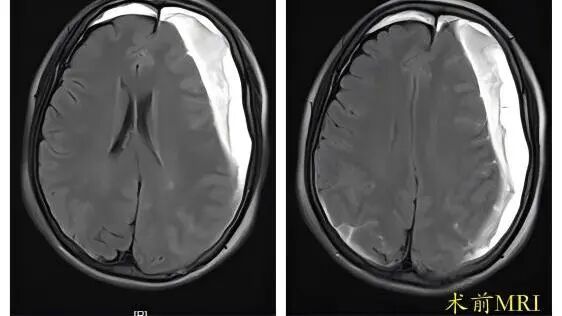

82岁的周奶奶(化名)近期出现神志恍惚、寡言少语、肢体无力、行走困难甚至小便失禁,家人起初误以为是“老年痴呆”。症状加重后送至贵州航天医院,经影像检查确诊为“慢性硬膜下血肿”。颅内较大血肿压迫脑组织,导致了这些神经功能损害。我院神经外科团队采用“微创引流”手术成功清除了血肿。术后1周,周奶奶康复出院;术后1月复查显示,受压脑组织复位良好,血肿无复发。 常见诱因与特点 该病多见于伴有脑萎缩的老年人,轻微头部外伤(如晃动、颠簸)即可撕裂脑表面脆弱的小静脉,造成缓慢出血,在脑萎缩、低颅压等因素影响下,血肿可能逐渐增大。典型症状包括记忆力减退、反应迟钝、嗜睡、肢体乏力等,易被忽视或误诊。 科学应对方案 少量无症状: 可尝试药物治疗,定期复查头部CT监测变化。 血肿增多或症状明显: 需及时就诊,颅骨钻孔微创引流术是首选且成熟的手术方式,能有效清除血肿、解除压迫。 防治复发: 脑膜中动脉栓塞术是预防复发的有效辅助手段。 温馨提示 老人轻微磕碰后若逐渐出现上述症状,应警惕慢性硬膜下血肿,即使受伤后早期颅脑CT未见异常,症状出现也需及时复诊,与高血压脑出血不同,慢性硬膜下血肿若能及早发现并规范治疗(如微创引流),通常预后良好。 注:部分图片来源于网络,如有侵权,请联系删除。 贵州航天医院 神经外科专家简介 廖洪民 神经外科党支部书记、主任,主任医师 临床擅长:从事神经外科临床工作30年,对颅脑损伤、脑肿瘤、脑血管病等具有丰富诊疗经验,擅长救治重症颅脑创伤、脑出血微创治疗、脑肿瘤显微手术治疗、脑立体定向手术等。 中国医师协会神经外科分会专科认证医师、贵州省医学会神经外科分会青年委员、遵义市医学会神经外科分会常务委员、遵义市中西医结合学会脑心同治专业委员会常务委员、中国生命关怀协会脑卒中救治及康复照护专业委员会委员、贵州省脑损伤评价质控中心专家库成员、遵义市脑损伤评价医疗质量控制中心专家。 朱家伟 神经外科副主任医师 临床擅长:从事神经外科工作26年,擅长颅脑损伤救治及脑出血微创手术。 遵义市医学会神经外科分会委员、遵义市中西医结合学会脑心同治专业委员会常务委员。 黄建军 神经外科副主任医师 临床擅长:从事神经外科工作20年,对神经外科常见病、急危重症有丰富诊疗经验,熟练掌握神经外科微创手术。 贵州航天医院 神经外科简介 基本情况 贵州航天医院神经外科于2008年独立建科,是首批国家卫健委能力建设和继续教育神经外科建设中心,贵州省神经外科介入联盟单位。现有专业技术人员17人,其中高级职称4人,中级5人,初级7人。 科室配备STORZ神经内镜系统、德国莱卡手术显微镜,国产西山开颅动力系统、蛇牌双极电凝、Mayfield头架等颅脑手术设备,以及无创和有创颅内压监护仪、正中神经刺激仪、脑循环康复治疗仪、排痰机、下肢康复训练器、气垫床、多参数监护仪等现代化医疗设备,为病区各种急、危、重患者的观察、监护和治疗保驾护航。 专科特色 (一)脑出血微创手术治疗 应用范围:各种病因导致的自发性脑出血(高血压脑出血、脑淀粉样血管病相关脑出血、抗凝药物相关脑出血等)。 技术优势:微创、精准、恢复快。 (二)颅脑病变显微切除术 应用范围:颅内各种占位性病变(脑囊肿、脑肿瘤等)。 技术优势:精确度高、创伤小、恢复快。 (三)颅脑创伤综合救治 应用范围:各种类型的颅脑损伤、创伤性颅内血肿及颅脑创伤并发症、后遗症等。 技术优势:快速精准诊断、个体化手术与监护、早期康复干预,伤者病死率低、并发症少。